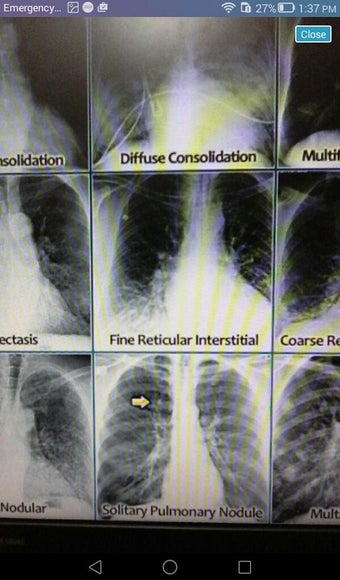

The Android Medical Records App by MedClin is a free medical records tracker app that allows users to store anamnesis, patient records, patient history, and health information. It is easy to use and provides numerous features such as username and password authentication, exporting medical data to Excel Sheet, and the ability to attach medical documents of any type. The app also has a smart search feature that allows users to search for patient information by name or ID, and even capture a photo for their profile.